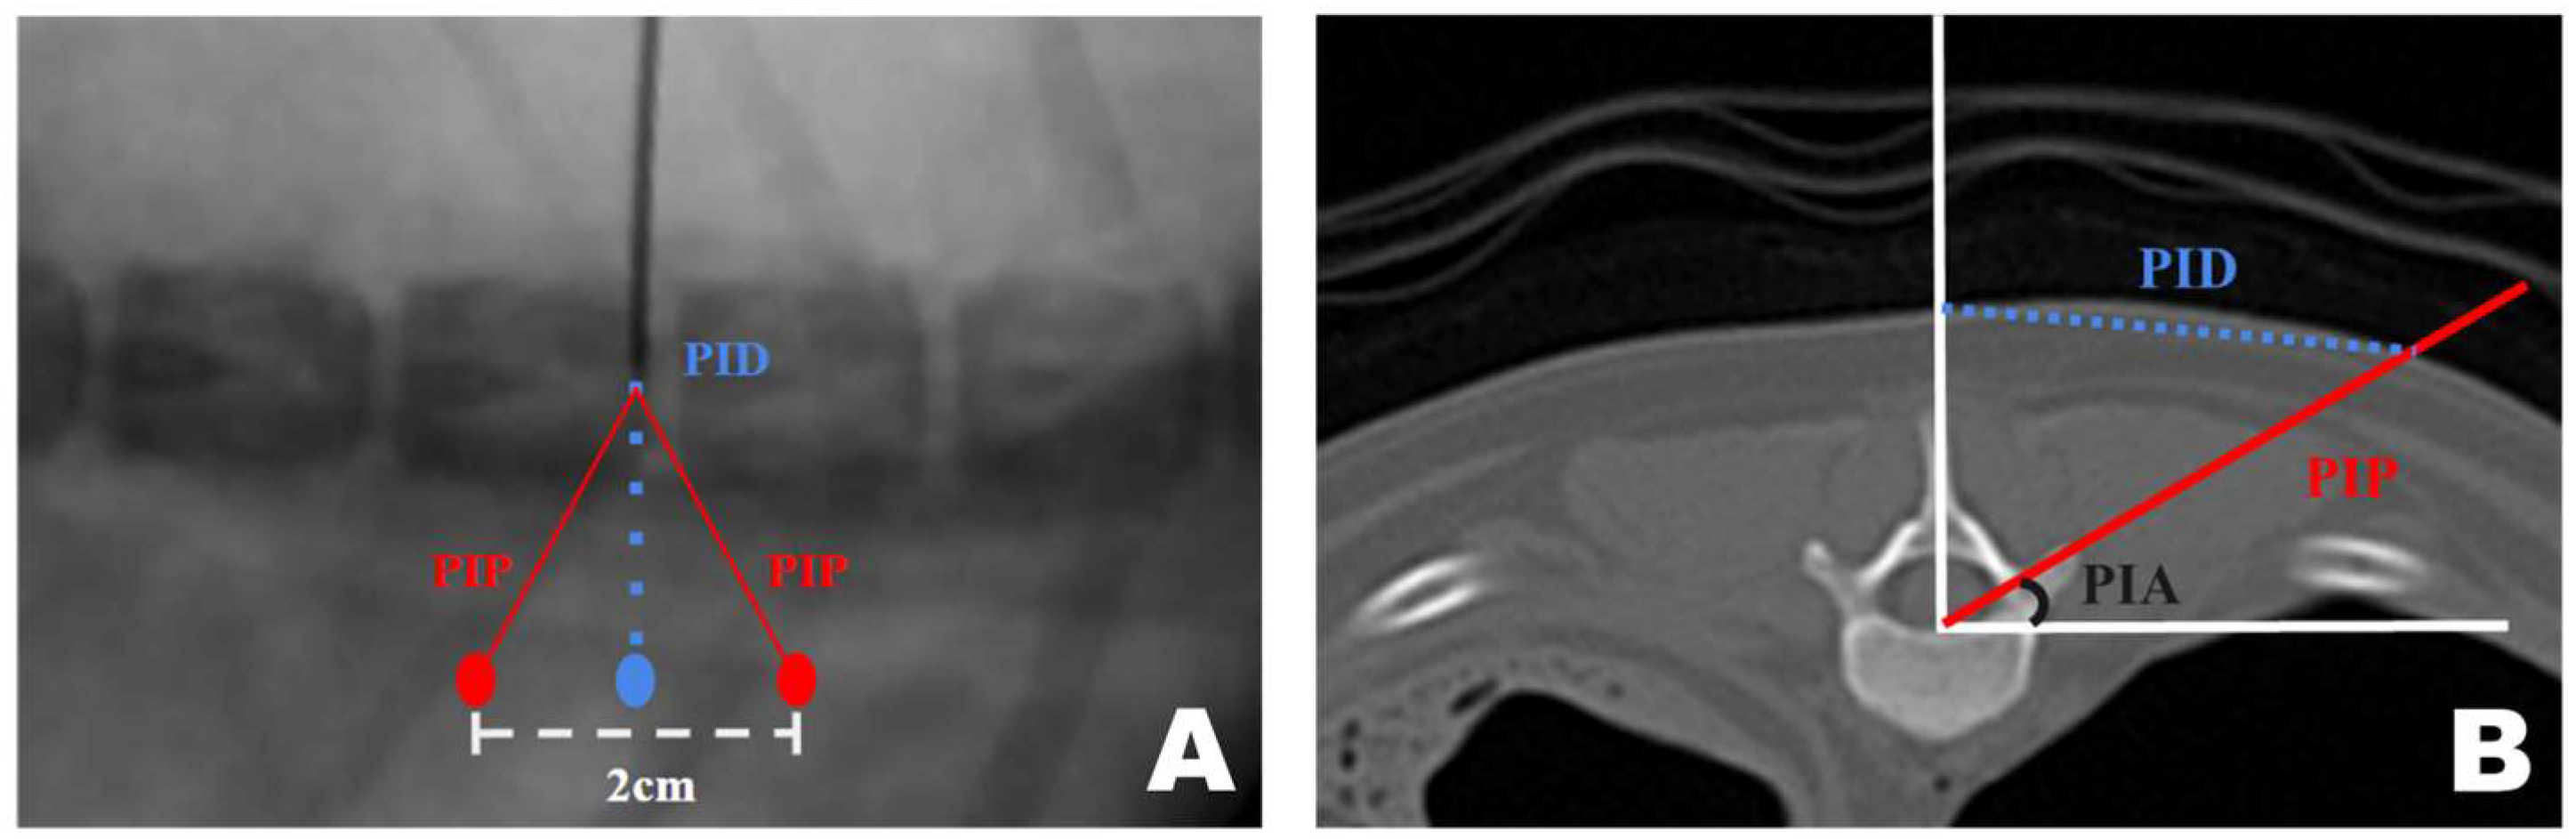

CT-based measurement values were obtained during surgical procedures. A pin was placed in the T12–13 intervertebral space. Line A, a straight line connecting the lateral margins of the spinous process in the surgeon’s direction, was established. Subsequently, parallel to line A, line B was drawn from the PID pin. At the PID on line B, two marks were made 1 cm apart, serving as insertion points for the scope and working portals, which were 2 cm apart [47,53,54]. Finally, line C was drawn from each portal to the pin, forming an isosceles triangular PIP (Figure 2A).

Figure 2.

Application of the CT-based measurement diagram to the actual patient. (A) Line A represents the lateral margin connecting the spinous processes, similar to the diagram. Since the pin was positioned at the center of the spinous process and line A connected the lateral margins, line A was drawn more laterally. The dotted line represents the portal insertion distance for drawing a line. The white arrow indicates the starting point of the scope portal, and the black arrow indicates the starting point of the working portal. Consistent with the diagram, the red line represents line C, corresponding to the portal insertion pathway. (B) The required inclination of the scope and working instrument is maintained at the portal insertion angle while being inserted along line C. (C) Verification using the dorsoventral view imaging confirmed that the scope and working instrument were correctly inserted into the accessory process and that an accurate triangle was formed. PIA, Portal Insertion Angle.

A transverse view of the T12 accessory process was obtained on the CT scan. A line was drawn from the midpoint of the ventral portion of the spinal canal to the T12 spinous process. Subsequently, a perpendicular line was drawn on the floor. A line connecting the accessory processes was drawn at the intersection of the two lines, which represented the actual portal insertion pathway (PIP). At this point, the distance from the skin portion on the spinous process line to the PIP was measured, which became the PID, determining the actual site of the skin incision. Furthermore, the angle between the floor line and PIP, which was maintained while inserting the portal from the PID-defined skin incision site to the accessory process, became the PIA (Figure 9A).

Figure 9.

Computed tomography (CT)-based measurement method applied for precise mini-hemilaminectomy. (A) Transverse CT view of the T12 accessory process. (B) Diagram of approach indicating the dorsoventral view of the T12-13 vertebra bone as seen during actual surgery through the fluoroscopy. PID, Portal Insertion Distance; PIP, Portal Insertion Pathway; PIA, Portal Insertion Angle.

The approach indication diagram was based on the DV position when the surgeon uses a CT-based measurement method during surgery. The distance between the two portals was 2 cm, and the procedure was conducted while maintaining a triangular formation as the portals were positioned (Figure 9B).